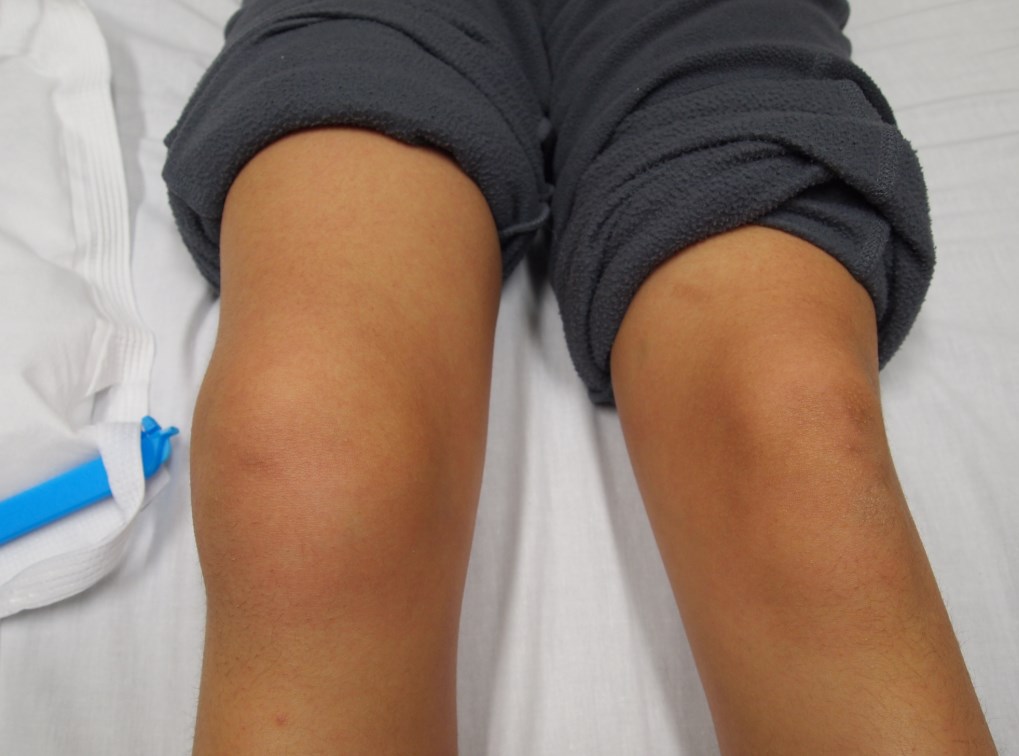

Ювенильный идиопатический артрит

Это хроническое воспалительное заболевание, развивается у детей в возрасте до 16 лет.

Сопровождается поражением суставов, часто именно коленных. Может приводить к необратимому разрушению хряща и подхрящевого отдела кости, вплоть до последующей инвалидизации.

Эффективность лечения напрямую зависит от возможности ранней диагностики (до того, как сформируются костные эрозии) и правильной оценки степени активности процесса.

Важная особенность этой болезни заключается в том, что около 70% больных с ранним ювенильным артритом не имеют видимых изменений на рентгенограммах. То есть если у ребенка болит колено без видимых изменений на обычном рентгене, лучше не откладывать и сделать МРТ, а не надеяться, что это пройдет само со временем. Иначе можно упустить время, необходимое для того, чтобы остановить процесс.

В данном случае преимущество МРТ в том, что она дает возможность оценить состояние синовиальной оболочки. Чаще всего – это признаки синовиита в виде наличия жидкости в полости сустава, утолщение синовиальной оболочки.

Важным является то, что на основании анализа толщины синовиальной оболочки и объема выпота можно отличить активный процесс от стадии ремиссии. Это кардинально меняет тактику лечения.